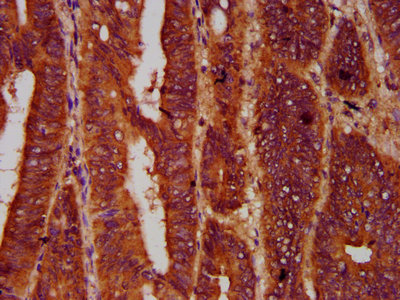

IHC image of CSB-PA842128LA01HU diluted at 1:600 and staining in paraffin-embedded human colon cancer performed on a Leica BondTM system. After dewaxing and hydration, antigen retrieval was mediated by high pressure in a citrate buffer (pH 6.0). Section was blocked with 10% normal goat serum 30min at RT. Then primary antibody (1% BSA) was incubated at 4°C overnight. The primary is detected by a biotinylated secondary antibody and visualized using an HRP conjugated SP system.